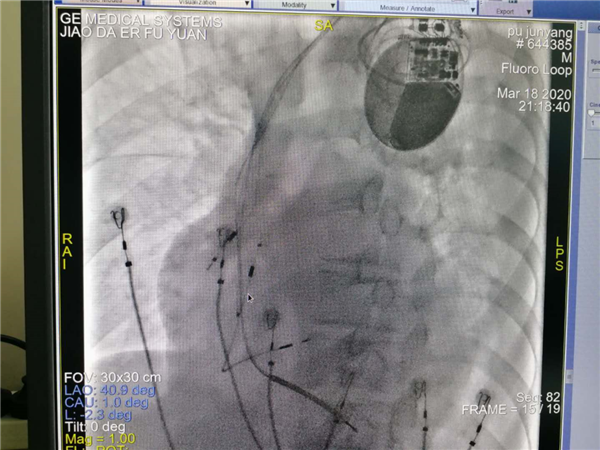

团队术前缜密讨论,充分考虑多个结局,多种策略。手术由郑强荪主任,韩振华副主任,薛嘉虹副教授,王新宏副教授及导管室护士王军、杨宏斌共同完成。团队先为患者行左心室电极植入冠状静脉窦的经典CRTD,但患者冠状静脉窦分支条件较差,左侧后支迂曲盘旋,给操作带来极大的困难,经多次尝试左室电极仍不能植入成功,郑强荪主任、韩振华副主任带领的团队迅速改变策略,与时俱进,决定行左束支区域起搏。另外患者在拔除原右室电极时又因电极与上腔静脉入口处粘连拔除困难,再次为手术带来障碍,最终经团队6小时的不懈努力,手术顺利完成。术后心电图QRS波群由原来的210ms缩窄为160ms,患者心功能明显改善。

术后起搏器留影